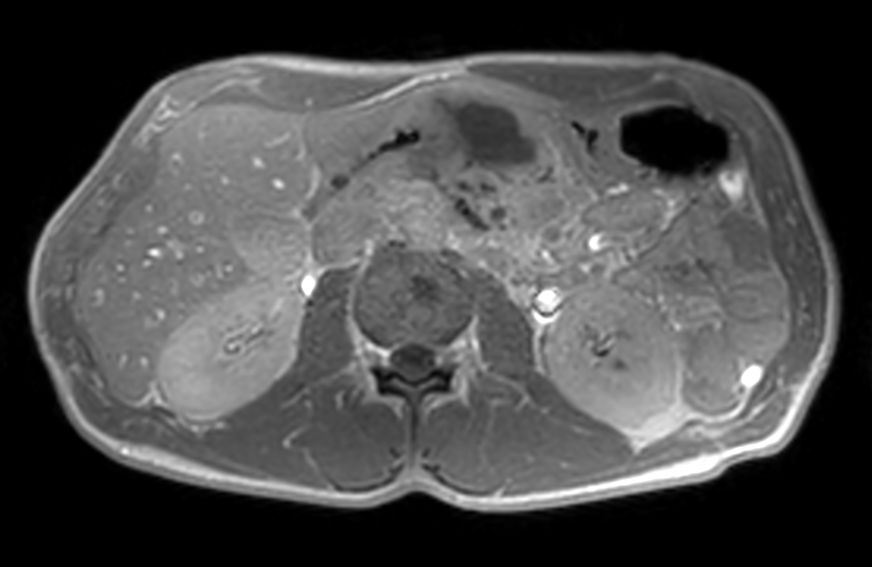

Axial T2w TSE single shot